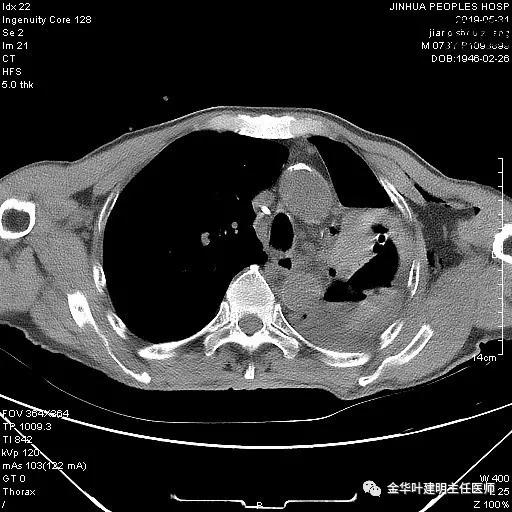

以上是肺窗表现,下面为纵隔窗影像:

因为引流出的胸液为血性,但感觉不是特别鲜,查血色素9.5 g/L,术前是12.7g/L。当时考虑胸腔内出血可能,较为纠结的是是否需要进胸探查。但鉴于血压正常、心率不快,一般情况良好,不似胸内大出血休克的表现,所以仍想继续观察保守治疗。